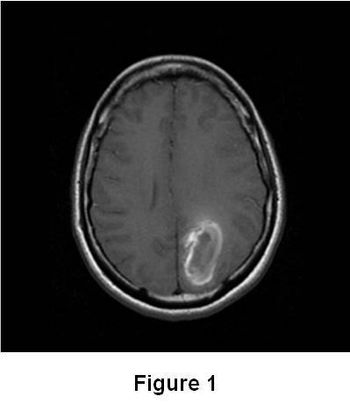

A 32 year old African American female presents with temporal region headaches, including sudden onset of extreme pain with no exacerbating or relieving factors, as well as peripheral vision loss in the right eye. MRI, MRA, and MRV added diagnosis.